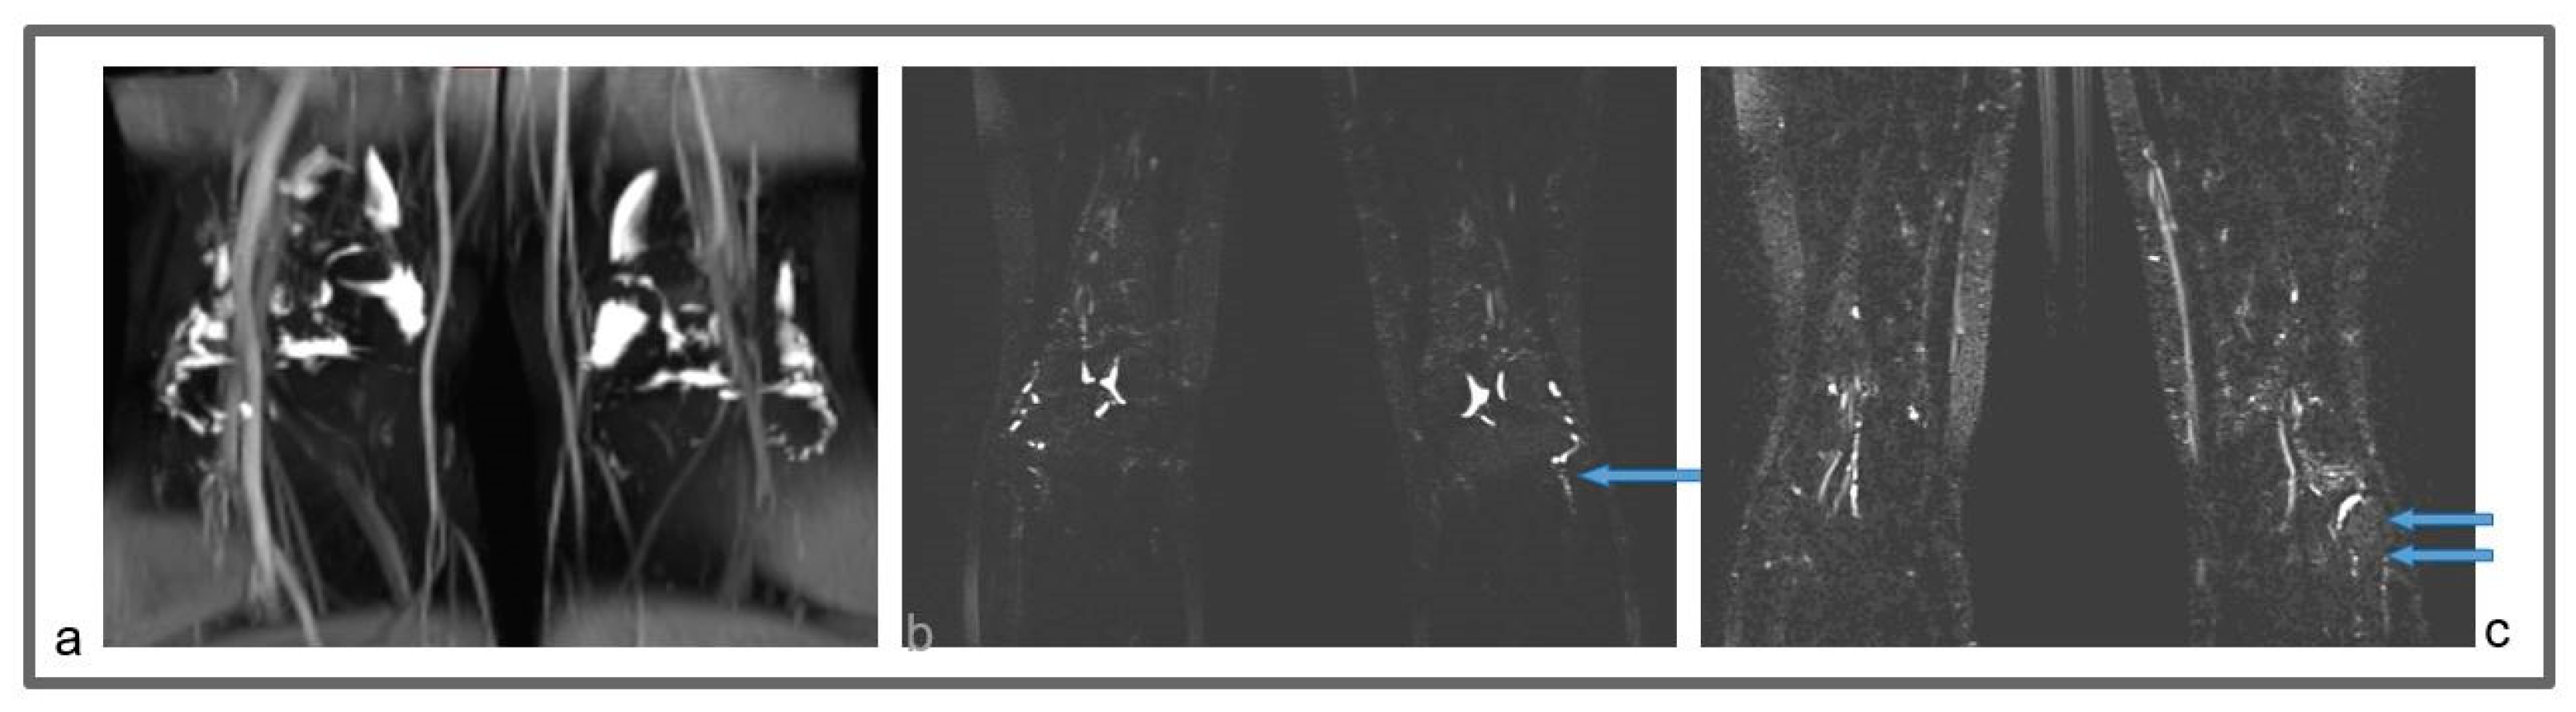

Figure 5.

Patient 2: Preoperative (a) and follow-up (b) non-contrast MR lymphography, 1 year after the surgical procedure, based on high-resolution heavily T2-weighted coronal sequences (turbo spin echo with repetition time 2870 ms, echo time 797 ms, field of view 380 × 380 mm, matrix 358 × 384, slice thickness 1 mm). The follow-up lymphography demonstrates the creation of new inguinal lymphatic vessels (b; blue arrows), that were not visible at the first examination (a).